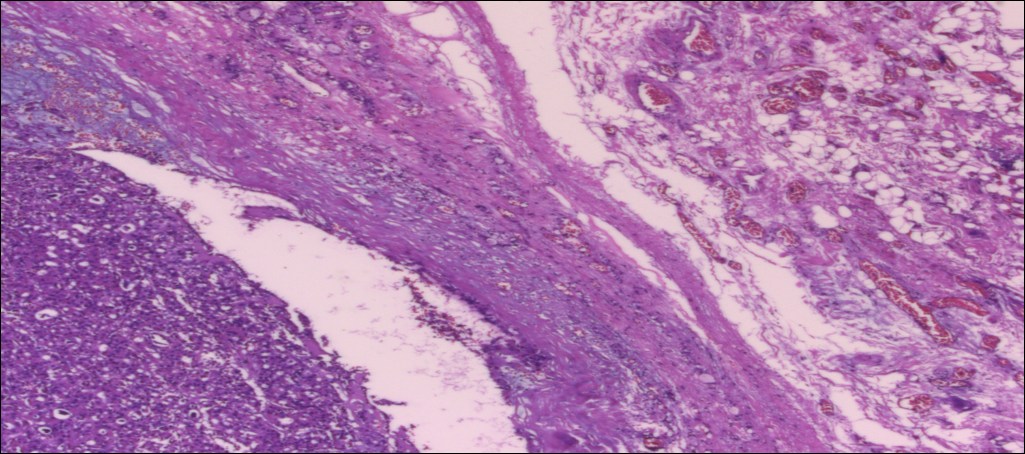

甲状腺嗜酸性细胞腺瘤

性别

女

年龄

71岁

临床诊断

肿物待查

一般病史

发现甲状腺肿物5个月

标本名称

甲状腺右叶及峡部肿物

大体所见

(甲状腺右叶及峡部):暗褐结节,直径6cm,包膜完整

肿物包膜完整,镜下未见明确包膜、脉管侵犯